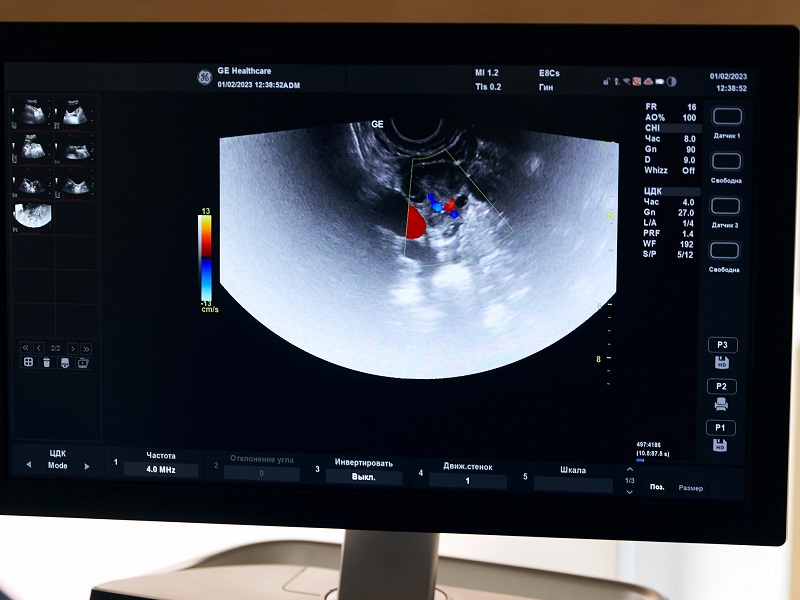

- УЗД молочних залоз;

Попередити такі випадки допомагає скринінг — профілактичні обстеження. Огляд у мамолога та проведення УЗД або мамографії допомагають виявляти пухлини на ранніх стадіях, коли вони ще не встигли поширитися на оточуючі тканини і метастазувати.

До 30-35 років для скринінгу застосовується УЗД, надалі — мамографія, яку з 40 до 50 років проходять раз на 2 роки, після 50 років — щорічно. Мамолог може порекомендувати інший графік скринінгових обстежень, якщо пацієнтка входить до групи ризику.